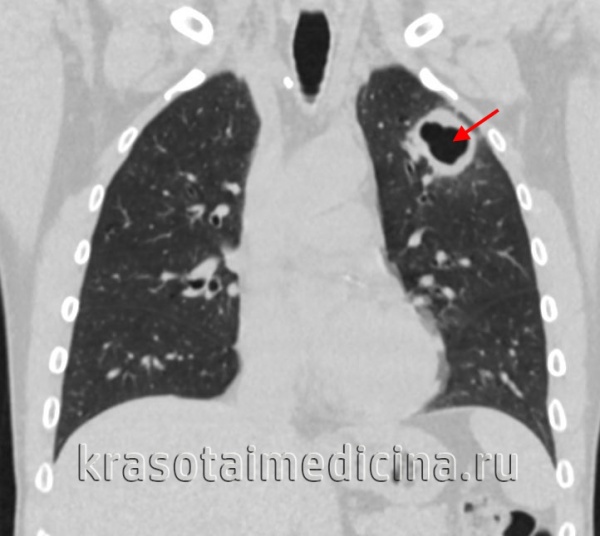

- Лучевая диагностика.Рентгенография легких является обязательным диагностической процедурой, позволяющей выявить характер изменений в легочной ткани (инфильтративный, очаговый, кавернозный, диссеминированный и т. д.), определить локализацию и распространенность патологического процесса. Выявление кальцинированных очагов указывает на ранее перенесенный туберкулезный процесс и требует уточнения данных с помощью КТ или МРТ легких.

2. Методы лучевой диагностики: рентгенография, рентгеноскопия, линейная томография, компьютерная томография, УЗИ-диагностика. Составляется протокол скиалогического исследования в соответствии со схемой описания рентгенограммы и делается заключение.

Большое внимание следует уделить описанию и интерпретации данных архива рентгенологического обследования, поскольку данный метод позволяет определить форму, локализацию и фазу туберкулеза органов дыхания.

Задание: описать одну обзорную рентгенограмму в прямой проекции включая общую характеристику снимка курируемого больного в соответствии со схемой описания рентгенограмм, сделать зарисовку рентгенологических изменений, выявленных у больного.